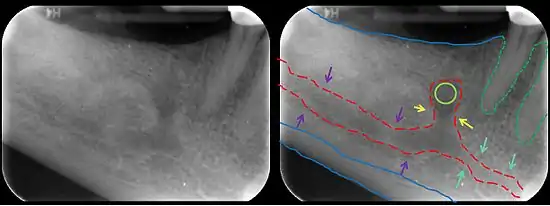

The mandibular incisive canal (indicated here by coral green arrows) continuing anteriorly (to the right) from the mandibular canal (purple arrows) after the mental foramen (light green circle)

In human anatomy, the mandibular canal is a canal within the mandible that contains the inferior alveolar nerve, inferior alveolar artery, and inferior alveolar vein. It runs obliquely downward and forward in the ramus, and then horizontally forward in the body, where it is placed under the alveoli and communicates with them by small openings.

On arriving at the incisor teeth, it turns back to communicate with the mental foramen, giving off a small canal known as the mandibular incisive canal, which run to the cavities containing the incisor teeth.[1] It carries branches of the inferior alveolar nerve and artery.